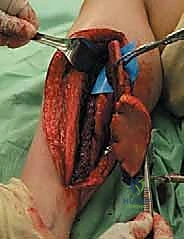

المرحلة الثانية: استئصال الطعم العظمي (Harvesting the Graft)

يقوم الجراح بعمل شق دقيق في الساق لاستخراج الجزء المطلوب من عظمة الشظية. الخطوة الأكثر حساسية هنا هي تسليك الشريان والوريد الشظوي الملتصقين بالعظمة دون إتلافهما، وقطعهما فقط عندما يكون موقع الاستقبال جاهزاً تماماً لتقليل فترة انقطاع الدم (Ischemia time).

المرحلة الثالثة: تحضير موقع الاستقبال (Recipient Site Preparation)

في الطرف المصاب (سواء كان الفخذ، القصبة، أو الذراع)، يتم تنظيف الفجوة العظمية بالكامل وإزالة أي أنسجة ميتة أو ندبات. ثم يتم تحديد شريان ووريد سليمين في هذه المنطقة لاستخدامهما في التوصيل.